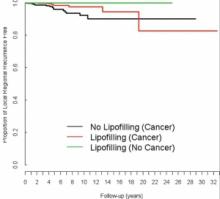

RECONSTRUCTION MAMMAIRE: L'injection de graisse n'augmente pas le risque de cancer

Actualité publiée il y a 10 années 2 moisOBÉSITÉ: L'interrupteur épigénétique qui rend l'un maigre et l'autre obèse